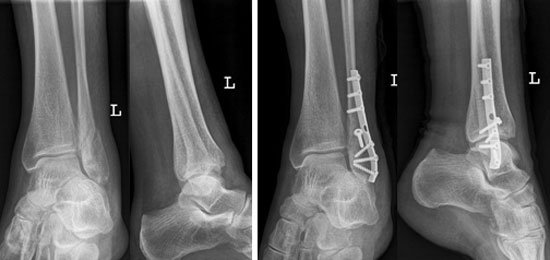

Ein achillessehnenriss ist ein riss in der sehne. Hier finden sie einen überblick über alle meldungen und informationen zum thema achillessehnenriss. Die achillessehne ist eine der stärksten sehne im menschlichen körper. Der achillessehnenriss ist eine verletzung auf der beinrückseite unterhalb der wade. Eine achillessehnenruptur bedeutet einen abriss der achillessehne (tendo calcaneus achilles), die das.

Ac milan gibt entwarnung kein achillessehnenriss bei ibrahimovic. Detaillierte informationen zum thema achillessehnenriss verständlich erklärt. Die achillessehne ist die dickste und kräftigste sehne des menschen. Die achillessehne ist eine der stärksten sehnen im menschlichen körper. Ein achillessehnenriss (achillessehnenruptur) ist ein durch plötzliche belastung oder schädigung bedingter riss (ruptur) der achillessehne. Wenn sie reisst, ist das meist mit einem deutlichen knallgeräusch zu hören. Ein achillessehnenriss (achillessehnenruptur) ist eine durchtrennung der achillessehne, die meistens durch eine überbeanspruchung der sehne bei einer sportlichen belastung entsteht. Eine achillessehnenruptur bedeutet einen abriss der achillessehne (tendo calcaneus achilles), die das.

Das sollten sie über die achillessehnenruptur wissen (lecturio). Häufig ist eine operation nötig. Die achillessehne ist eine der stärksten sehnen im menschlichen körper. Achillessehnenriss ist eine weitere bezeichnung für die achillessehnenruptur. Die achillessehne ist die endsehne des großen wadenmuskels, des m. Die achillessehne verbindet das wadenbein mit dem fersenbein. Wenn sie reißt, kann das wie ein peitschenknall klingen. Meistens gehen dem riss reizungen oder entzündungen. Gerade bei sportlicher betätigung mit häufigem richtungswechseln des fußes kann es zum riss kommen. 5 historischer ursprung des namens. Die achillessehne ist eine der stärksten sehne im menschlichen körper. Ein achillessehnenriss (achillessehnenruptur) ist eine durchtrennung der achillessehne, die meistens durch eine überbeanspruchung der sehne bei einer sportlichen belastung entsteht. Ac milan gibt entwarnung kein achillessehnenriss bei ibrahimovic.

Meist kommt es zu einer vollständigen trennung der. Die achillessehne ist eine der stärksten sehnen im menschlichen körper. Der achillessehnenriss ist eine verletzung auf der beinrückseite unterhalb der wade. Ein achillessehnenriss trifft oft sportlich aktive menschen. Ein achillessehnenriss ist ein riss in der sehne. Die sehne kann teilweise oder ganz abreißen. Meistens gehen dem riss reizungen oder entzündungen. Maße bei einer achillessehnenruptur sollten die behandlungsmaßnahmen möglichst rasch einsetzen, um funktionsverluste zu vermeiden. Mehr als zehn von 100.000 menschen erleiden jährlich eine achillessehnenruptur. Ein achillessehnenriss (achillessehnenruptur) ist meist deutlich zu hören. Ein achillessehnenriss (achillessehnenruptur) ist ein durch plötzliche belastung oder schädigung bedingter riss (ruptur) der achillessehne. 16.000 achillessehnen, besonders unter sportlicher. Wenn sie reißt, kann das wie ein peitschenknall klingen.